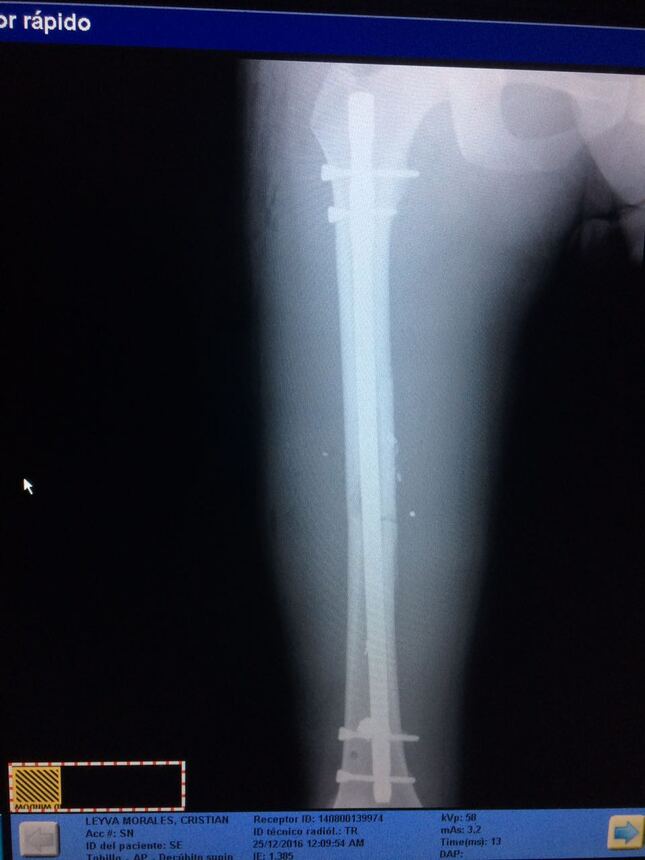

TRATAMIENTO DE FRACTURAS - GALERÍA DE IMÁGENES

Clavo de fémur